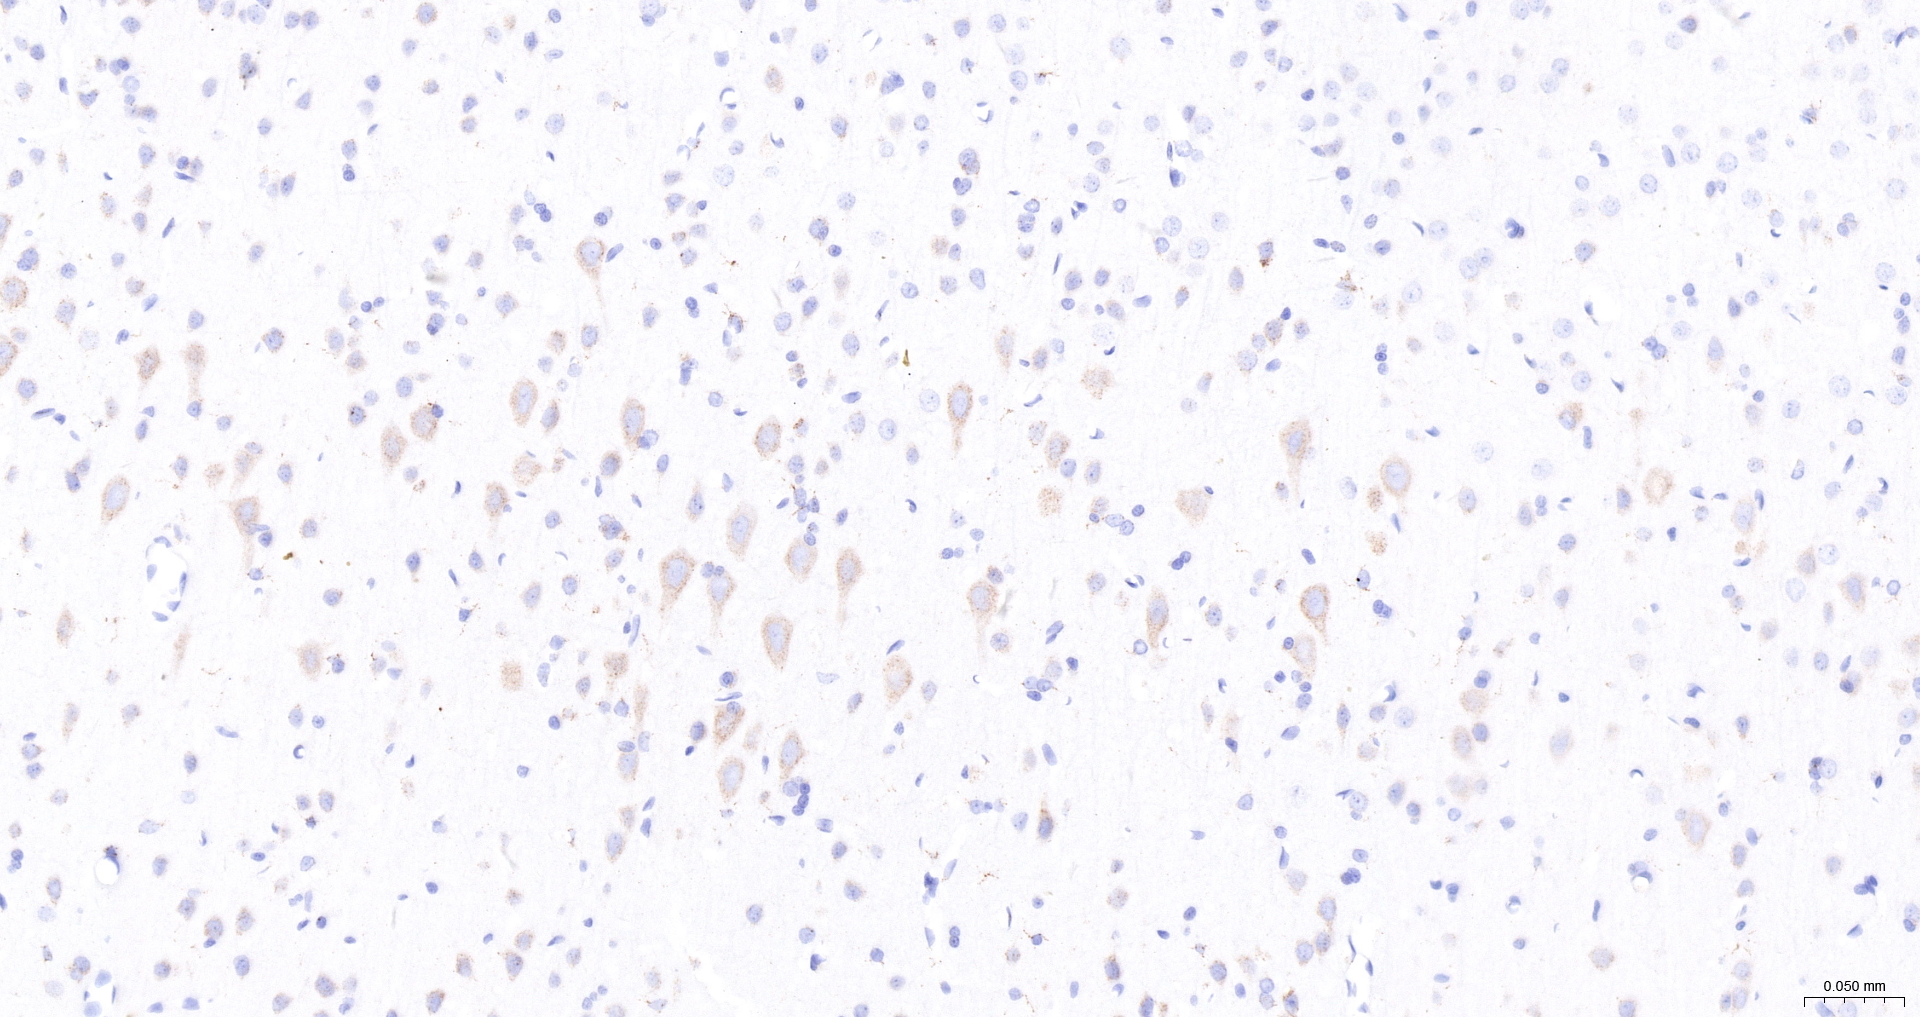

• IHC-P

IHC-P IHC-P1:100-200